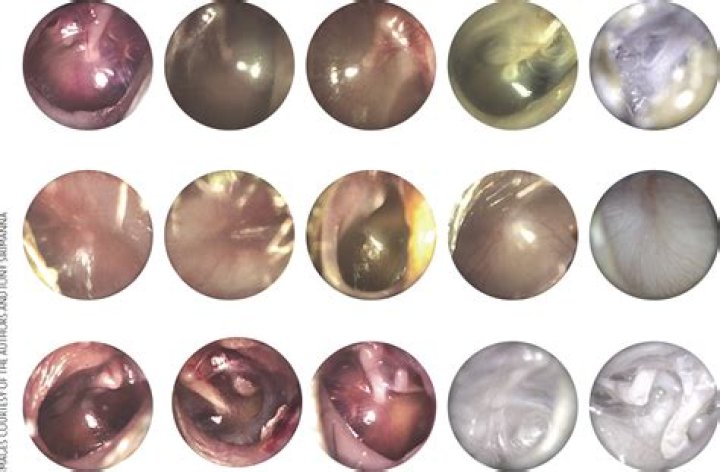

What color is ear infection drainage?